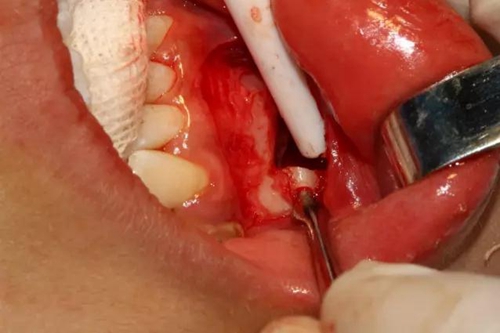

為了減少骨創(chuàng),“T”型分割牙冠

去除冠部

同時在剩余的根部斷面4MM下,預(yù)備2MM的溝槽,通過剝離子的三角尖端將牙體推出